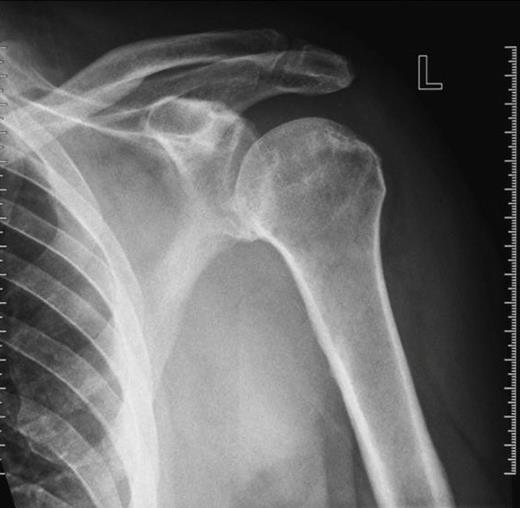

Ten weeks later a repeat orthopaedic review was requested by the rehabilitation team. There had been a slow onset and progression of oedema in the arm, with gradual progression of neurological deficit to the point at which the arm became useless and insensate. An increase in axillary bruising was noted. Also, the patient required a three-unit blood transfusion for a drop in haemoglobin six weeks after the injury. There was a thrill over the whole pectoral region and signs of venous hypertension in the arm. The left radial, ulnar and brachial pulses were normal. Repeat X ray showed subluxation of the left shoulder joint (figure 2). CT angiography revealed a distal axillary pseudoaneurysm with a sac of 15cm diameter (figure 3).

Repeat X-ray of left shoulder demonstrating subluxation of the head of the humerus